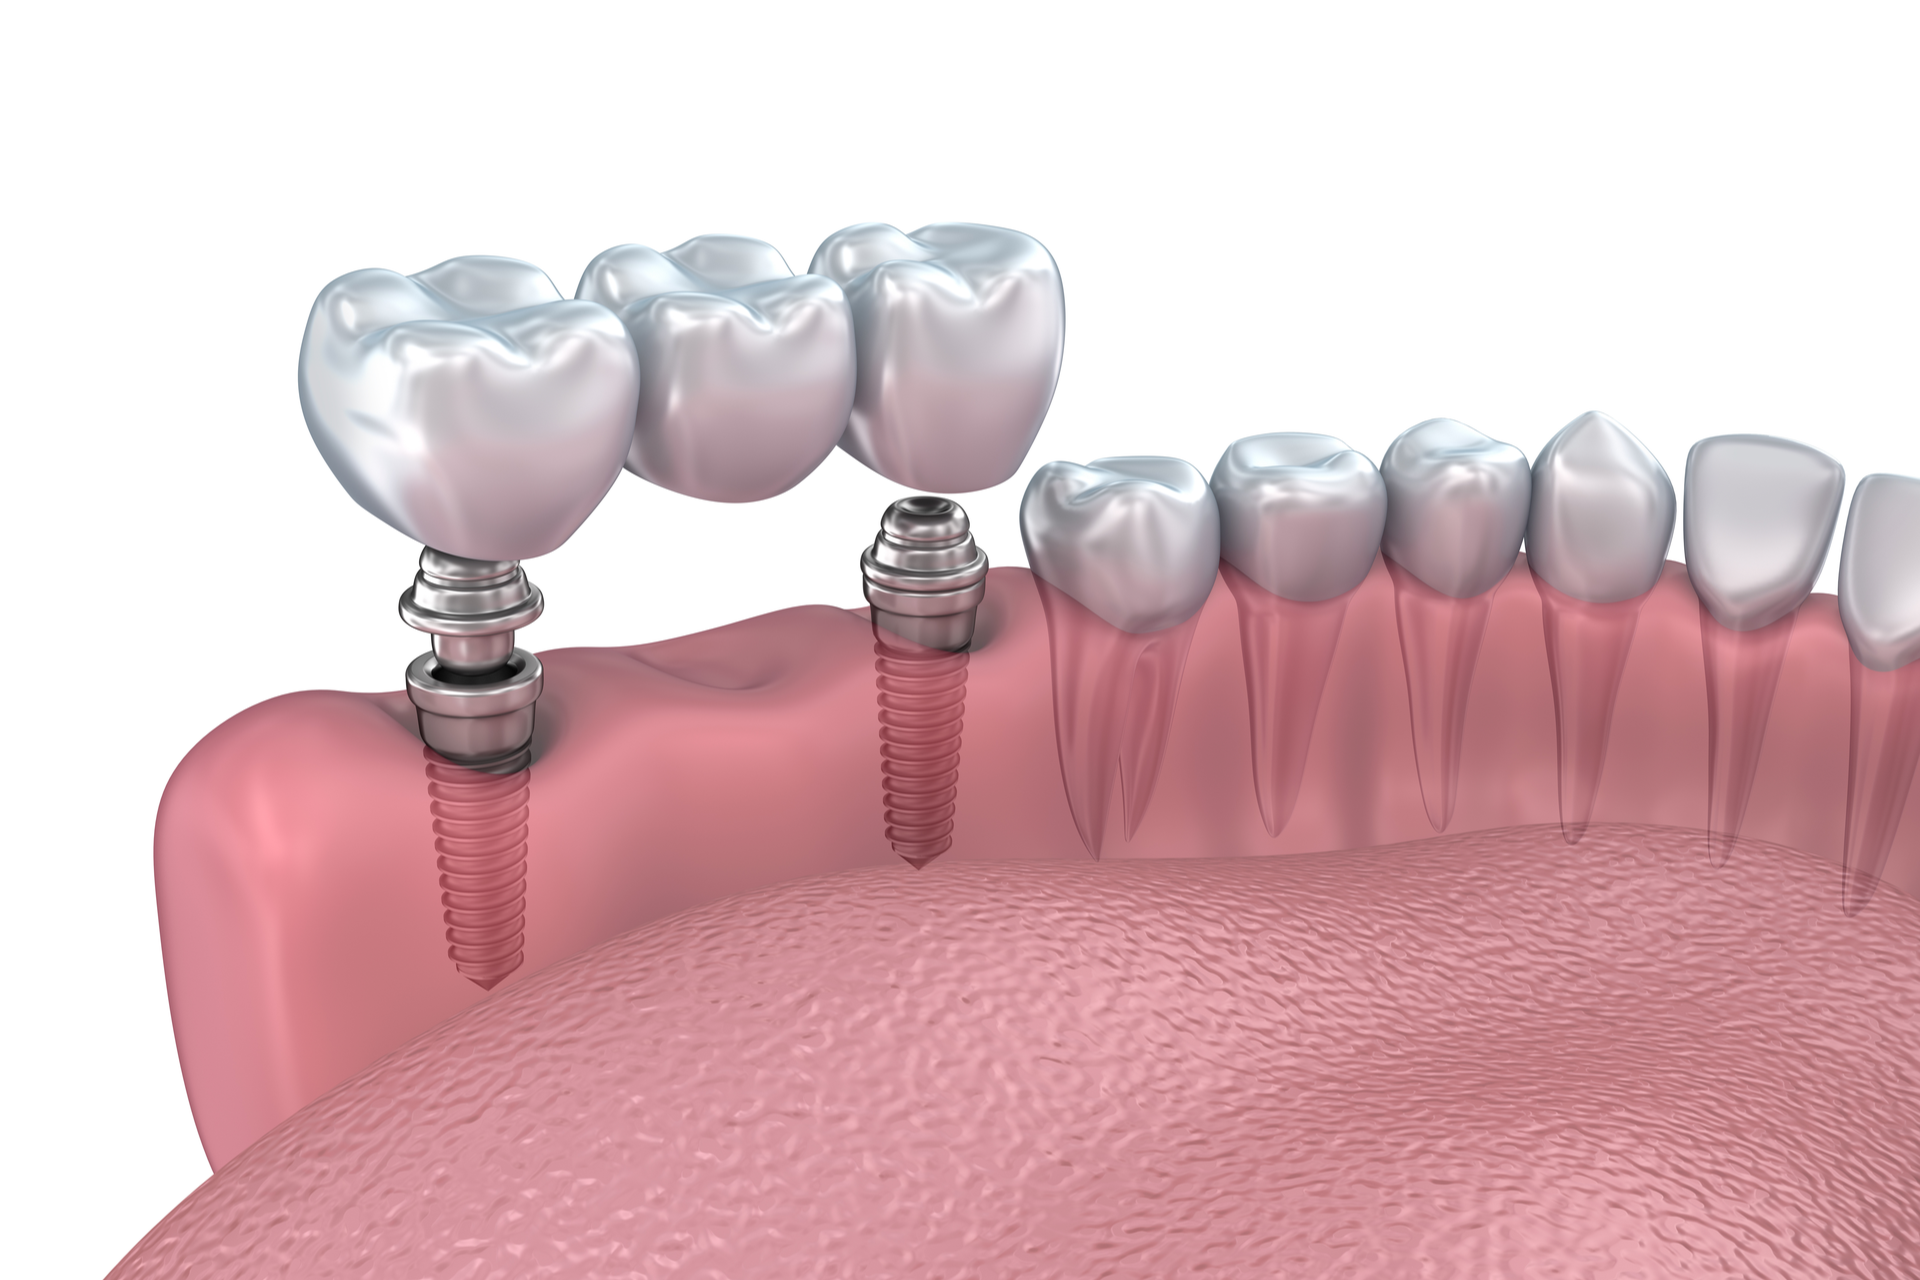

Le soluzioni terapeutiche, con l'utilizzo di impianti osteointegrati, rappresentano la routine dello studio per il ripristino di elementi dentali mancanti - da quasi trenta anni: l' impianto dentale è un dispositivo medico inserito nell'osso che vicaria la radice del dente e sul quale, tramite l'esecuzione di un perno, è possibile l'applicazione di una corona protesica.

Il mercato offre oggi tantissime varietà di impianti dentali che variano nella lunghezza, nel diametro e nella forma, rendendo possibile il loro inserimento anche in zone di ridotta disponibilità ossea verticale (senza dover ricorrere a complesse procedure di aumento volumetrico dell'osso). E’ possibile quindi utilizzare i più adatti, a seconda delle caratteristiche ossee individuali, scegliendo tra quelli proposti dalle varie aziende. Le aziende che preferisco sono Straumann, Sweeden Martina, Astra, Defcon, Phibo Geass: per me le più affidabili e collaudate per qualità di materiali e protocolli di controllo di produzione.

Le soluzioni protesiche che si avvalgono di impianti sono molteplici: fisse (preferibili) o mobili. Quelle fisse possono variare dal ripristino protesico di un elemento mancante a tutta l’arcata. Solo per citare qualche esempio, nel settore anteriore è possibile eseguire un impianto dentale post estrattivo immediato con applicazione di un provvisorio nella stessa seduta, così come in una tecnica detta All On Four utilizzata nelle edentulie totali è possibile, avvalendosi di una dima chirurgica (realizzata preliminarmente con tecnica Cad -cam) come guida per il posizionamento degli impianti stessi, programmare l’applicazione di una protesi totale provvisoria fissa in un’unica seduta.